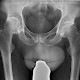

App zur mobilen Nutzung dreidimensionaler Scans von Computer- oder Kernspintomographen, Ultraschall oder Positronenemissionstomographen.

Mit der App könnten sich Ärzte noch schneller absprechen, die Patienten am Krankenbett besser informieren oder den Studierenden und in der Weiterbildung genauere Erläuterungen geben.

„Im Umfeld einer Hochleistungsklinik wie der MHH ist es selbstverständlich, dass Bilder und Befunde der Radiologie überall im Krankenhaus zur Verfügung stehen“, sagte der Leiter des Instituts für Diagnostische und Interventionelle Radiologie, Frank Wacker.

„Damit können Ärzte jetzt Bilder aus radiologischen Untersuchungen jederzeit überall auf dem Gelände abrufen“, sprach der MHH-Vizepräsident A. Tecklenburg.

Allerdings war dazu bisher eine Workstation erforderlich. „Die mobile App ist ideal für die Kollegen, die rasch und unabhängig von einem vollwertigen Bildschirmarbeitsplatz am Krankenbett oder im OP radiologische Bilder und Befunde benötigen“, erläuterte er.

Dank einer intelligenten Bildkompression seien die Ladezeiten für die Bilder einer Untersuchung relativ kurz, dennoch seien die Ansprüche an die drahtlosen Netzwerke „erheblich“. Ein besonderes Augenmerk legt das Zentrum für Informationsmanagement der MHH nach eigenen Angaben auf die Sicherheit der Datenübermittlung.